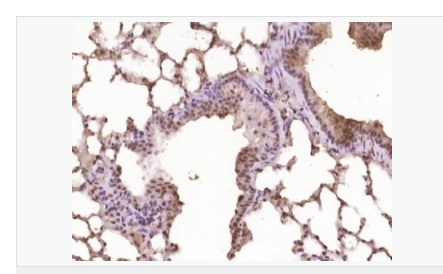

image.png